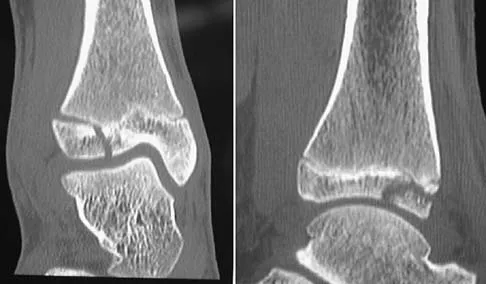

A 13-year-old girl injures her ankle playing soccer. Radiographs reveal a displaced Tillaux fracture. CT scans are shown in Figure 25. What is the most important consideration for appropriate management?

Explanation